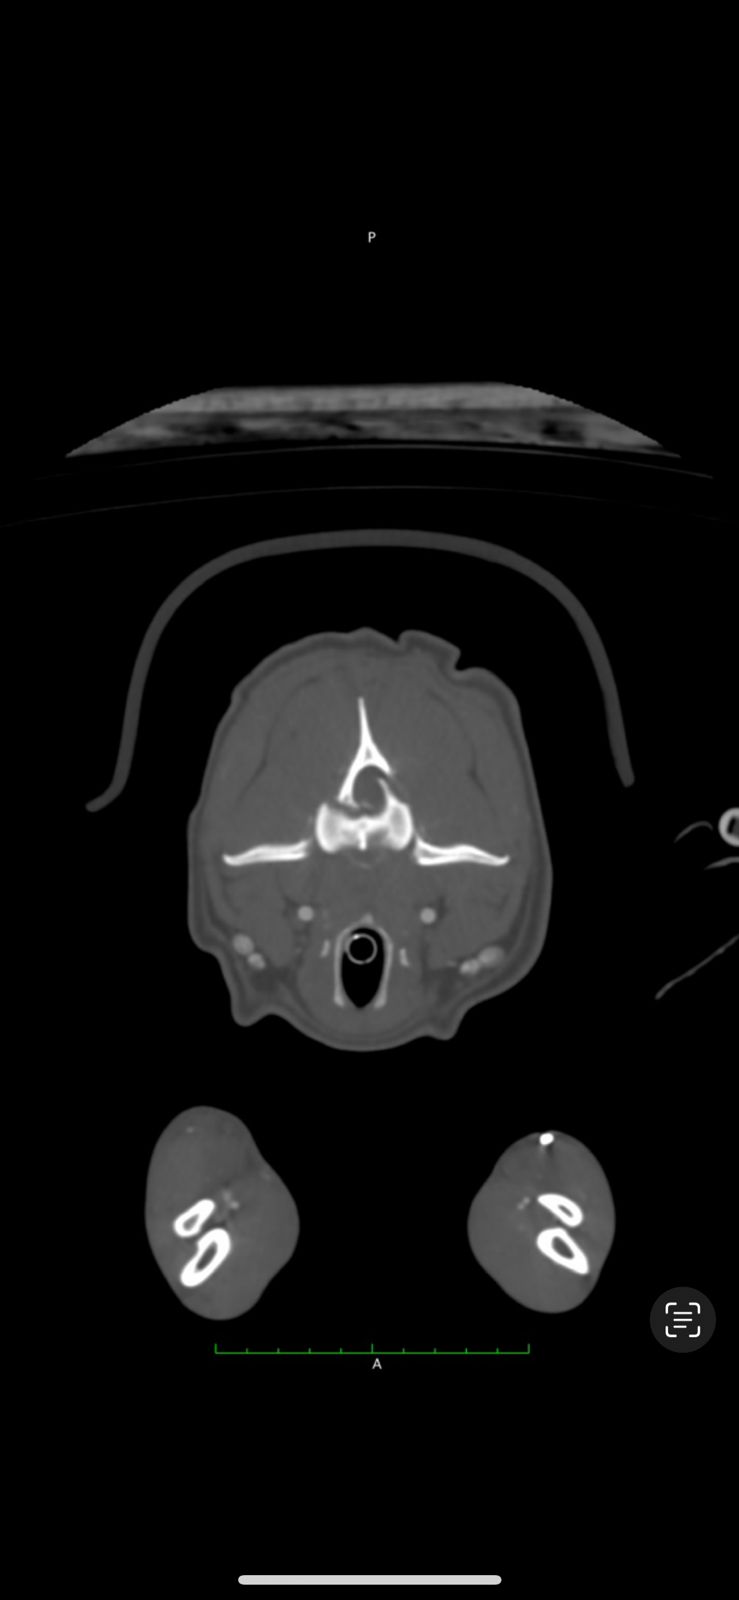

A thorough neurological examination followed by a CT scan revealed a C2 vertebral fracture with severe spinal cord compression along with a scapular fracture. Woody also experienced intense pain when flexing his neck. Given the risk of permanent damage, the surgical team decided to proceed with an advanced spinal fixation procedure using screws and PMMA.